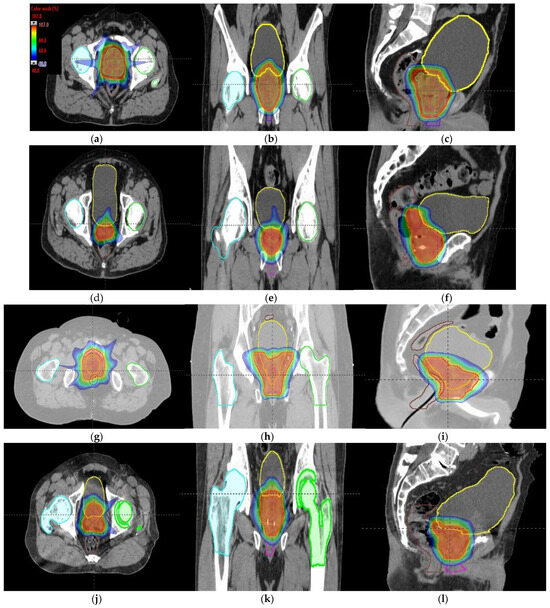

Figure 6.

Axial, coronal, and sagittal CT slices of prostate cancer patients 1 (a–c), 2 (d–f), 3 (g–i), and 4 (j–l). Dose distribution is displayed, showing isodose curves in a range from 40% (blue) to 107% (red) of the prescribed dose.

Tumor dose coverage and homogeneity presented acceptable values, i.e., V98% (%) ≥ 95% and V107% (%) ≤ 10%, for all MIBE studied (Table 2), except for 160 MeV. This was due to its inadequate range compared to the water equivalent thickness (WEL) from the entrance to the target for all gantry angles. Moreover, in Table 2, the values of the clinical goals show that 160 MeV allows for better protection of normal tissue, but the lack of coverage in PTV (except for the first patient) suggests the use of 180 MeV as the lowest value for MIBE. The color coding is the same as that used for Table 1. As a summary of the different plans, the DVHs are shown in Figure 5a–d and the axial, sagittal, and coronal slices of dose distributions are shown in Figure 6a–l. The dose distribution in patient 1 corresponded to a proton plan of 160 MeV MIBE, while for the other patients, the MIBE was 180 MeV.